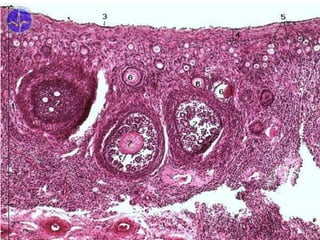

Folliculi ovarici tertiarii / vesiculosi

Tertiary follicles

• 2-5 mm

• Call-Exner‘s bodies (corpusculum intercellulare) → cavities

between follicular cells → coalesce to form one cavity (antrum

folliculi) filled with fluid (liquor folliculi)

• granulosa cells (epitheliocyti granulares; folilculocyti granulares)

form stratified epithelium = granulosa

• oocyte located peripherally (cumulus oophorus) surrounded by

zona pellucida and outward by granulosa cells (corona radiata)

• theca folliculi differentiates into:

•  theca interna  vessels + theca cells (endocrinocyti

thecales)  estrogens

•  theca externa – connective tissue (fibrocyti thecales)

29.05.2023

1 – folliculus

secundarius

2 – folliculocyti

3 – oocytus

4 – zona

pellucida

9 – theca folliculi